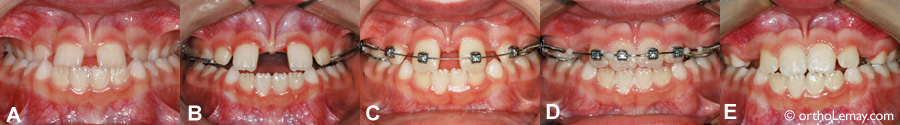

Fermeture d’un diastème de 5 mm en 5 mois

• (A) Une frénectomie labiale avait été faite auparavant dans l’espoir que le diastème se referme, ce qui était impossible et n’a rien donné comme résultat.

• (B) Pose des appareils fixes multi-bagues.

• (C) Après 5 mois de corrections orthodontiques.

• (D) Après l’enlèvement des appareils et qu’une gingivectomie ait été faite entre les incisives centrales.

➡ Pour en savoir plus sur ce cas et voir d’autres exemples de fermetures d’espaces et diastèmes.